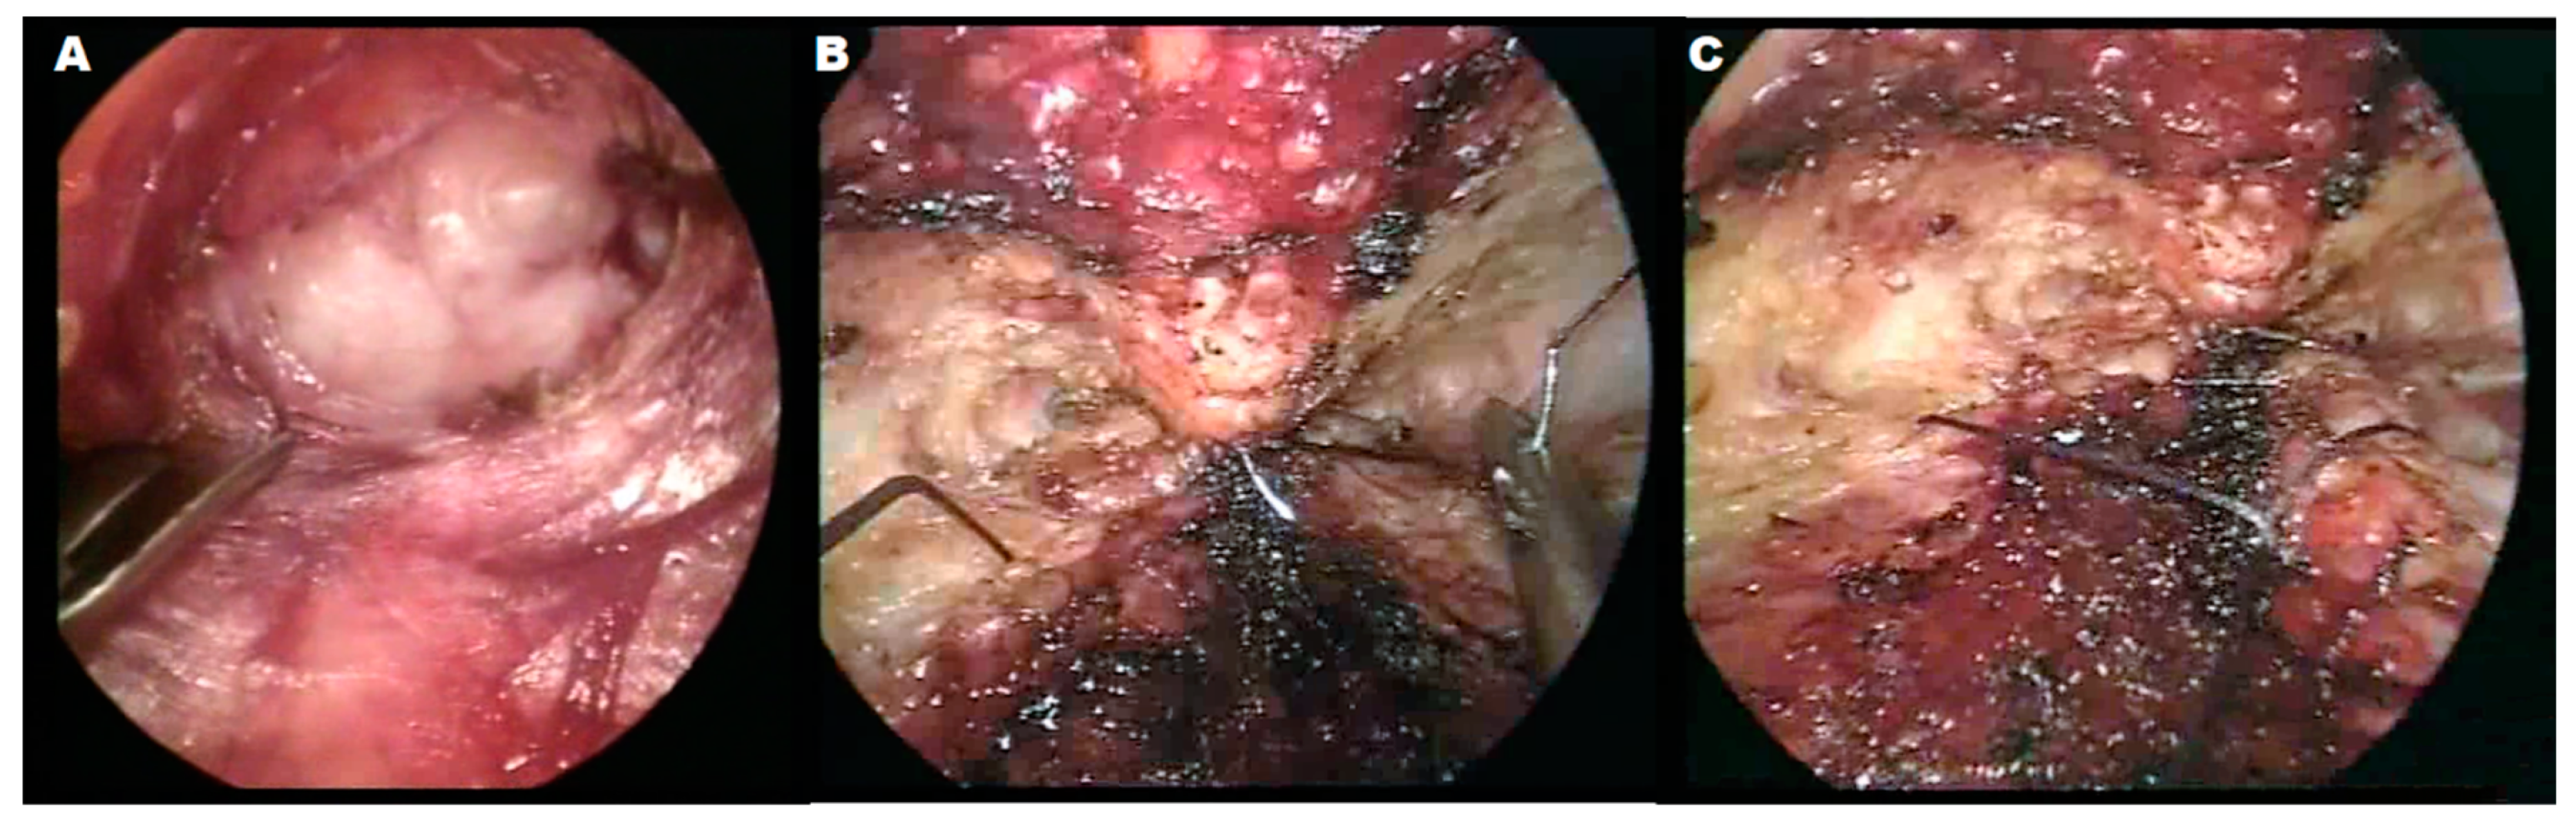

2.3. Surgical Technique